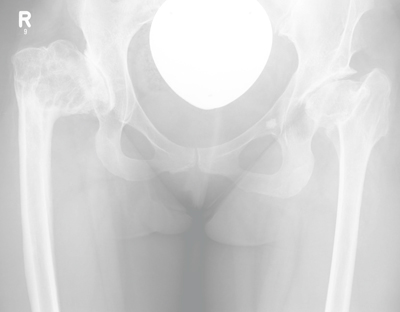

Hüfte

Fehlanlage des Hüftgelenkes ( Dysplasie )

Die unvollständige Ausbildung des Hüftgelenks ist eine der häufigsten angeborenen orthopädischen Erkrankungen. Mädchen bzw. Frauen sind davon häufiger betroffen als Jungen bzw. Männer. Wird sie im Säuglingsalter und in der Kindheit nicht ausreichend behandelt, treten im meist jungen Erwachsenenalter erste Beschwerden auf. Diese sind Ausdruck beginnenden Verschleisses, da Hüftkopf und Gelenkpfanne nicht schlüssig zueinander passen. Im Verlauf der Erkrankung entsteht eine Arthrose. Um diese möglichst lange hinauszuschieben oder gar zu vermeiden, besteht anfänglich die Möglichkeit, eine Umstellungsoperation des betroffenen Knochens (Becken- oder Oberschenkelknochen) durchzuführen. Bei fortgeschrittenem Verschleiss ist die Versorgung mit einer Endoprothese notwendig.